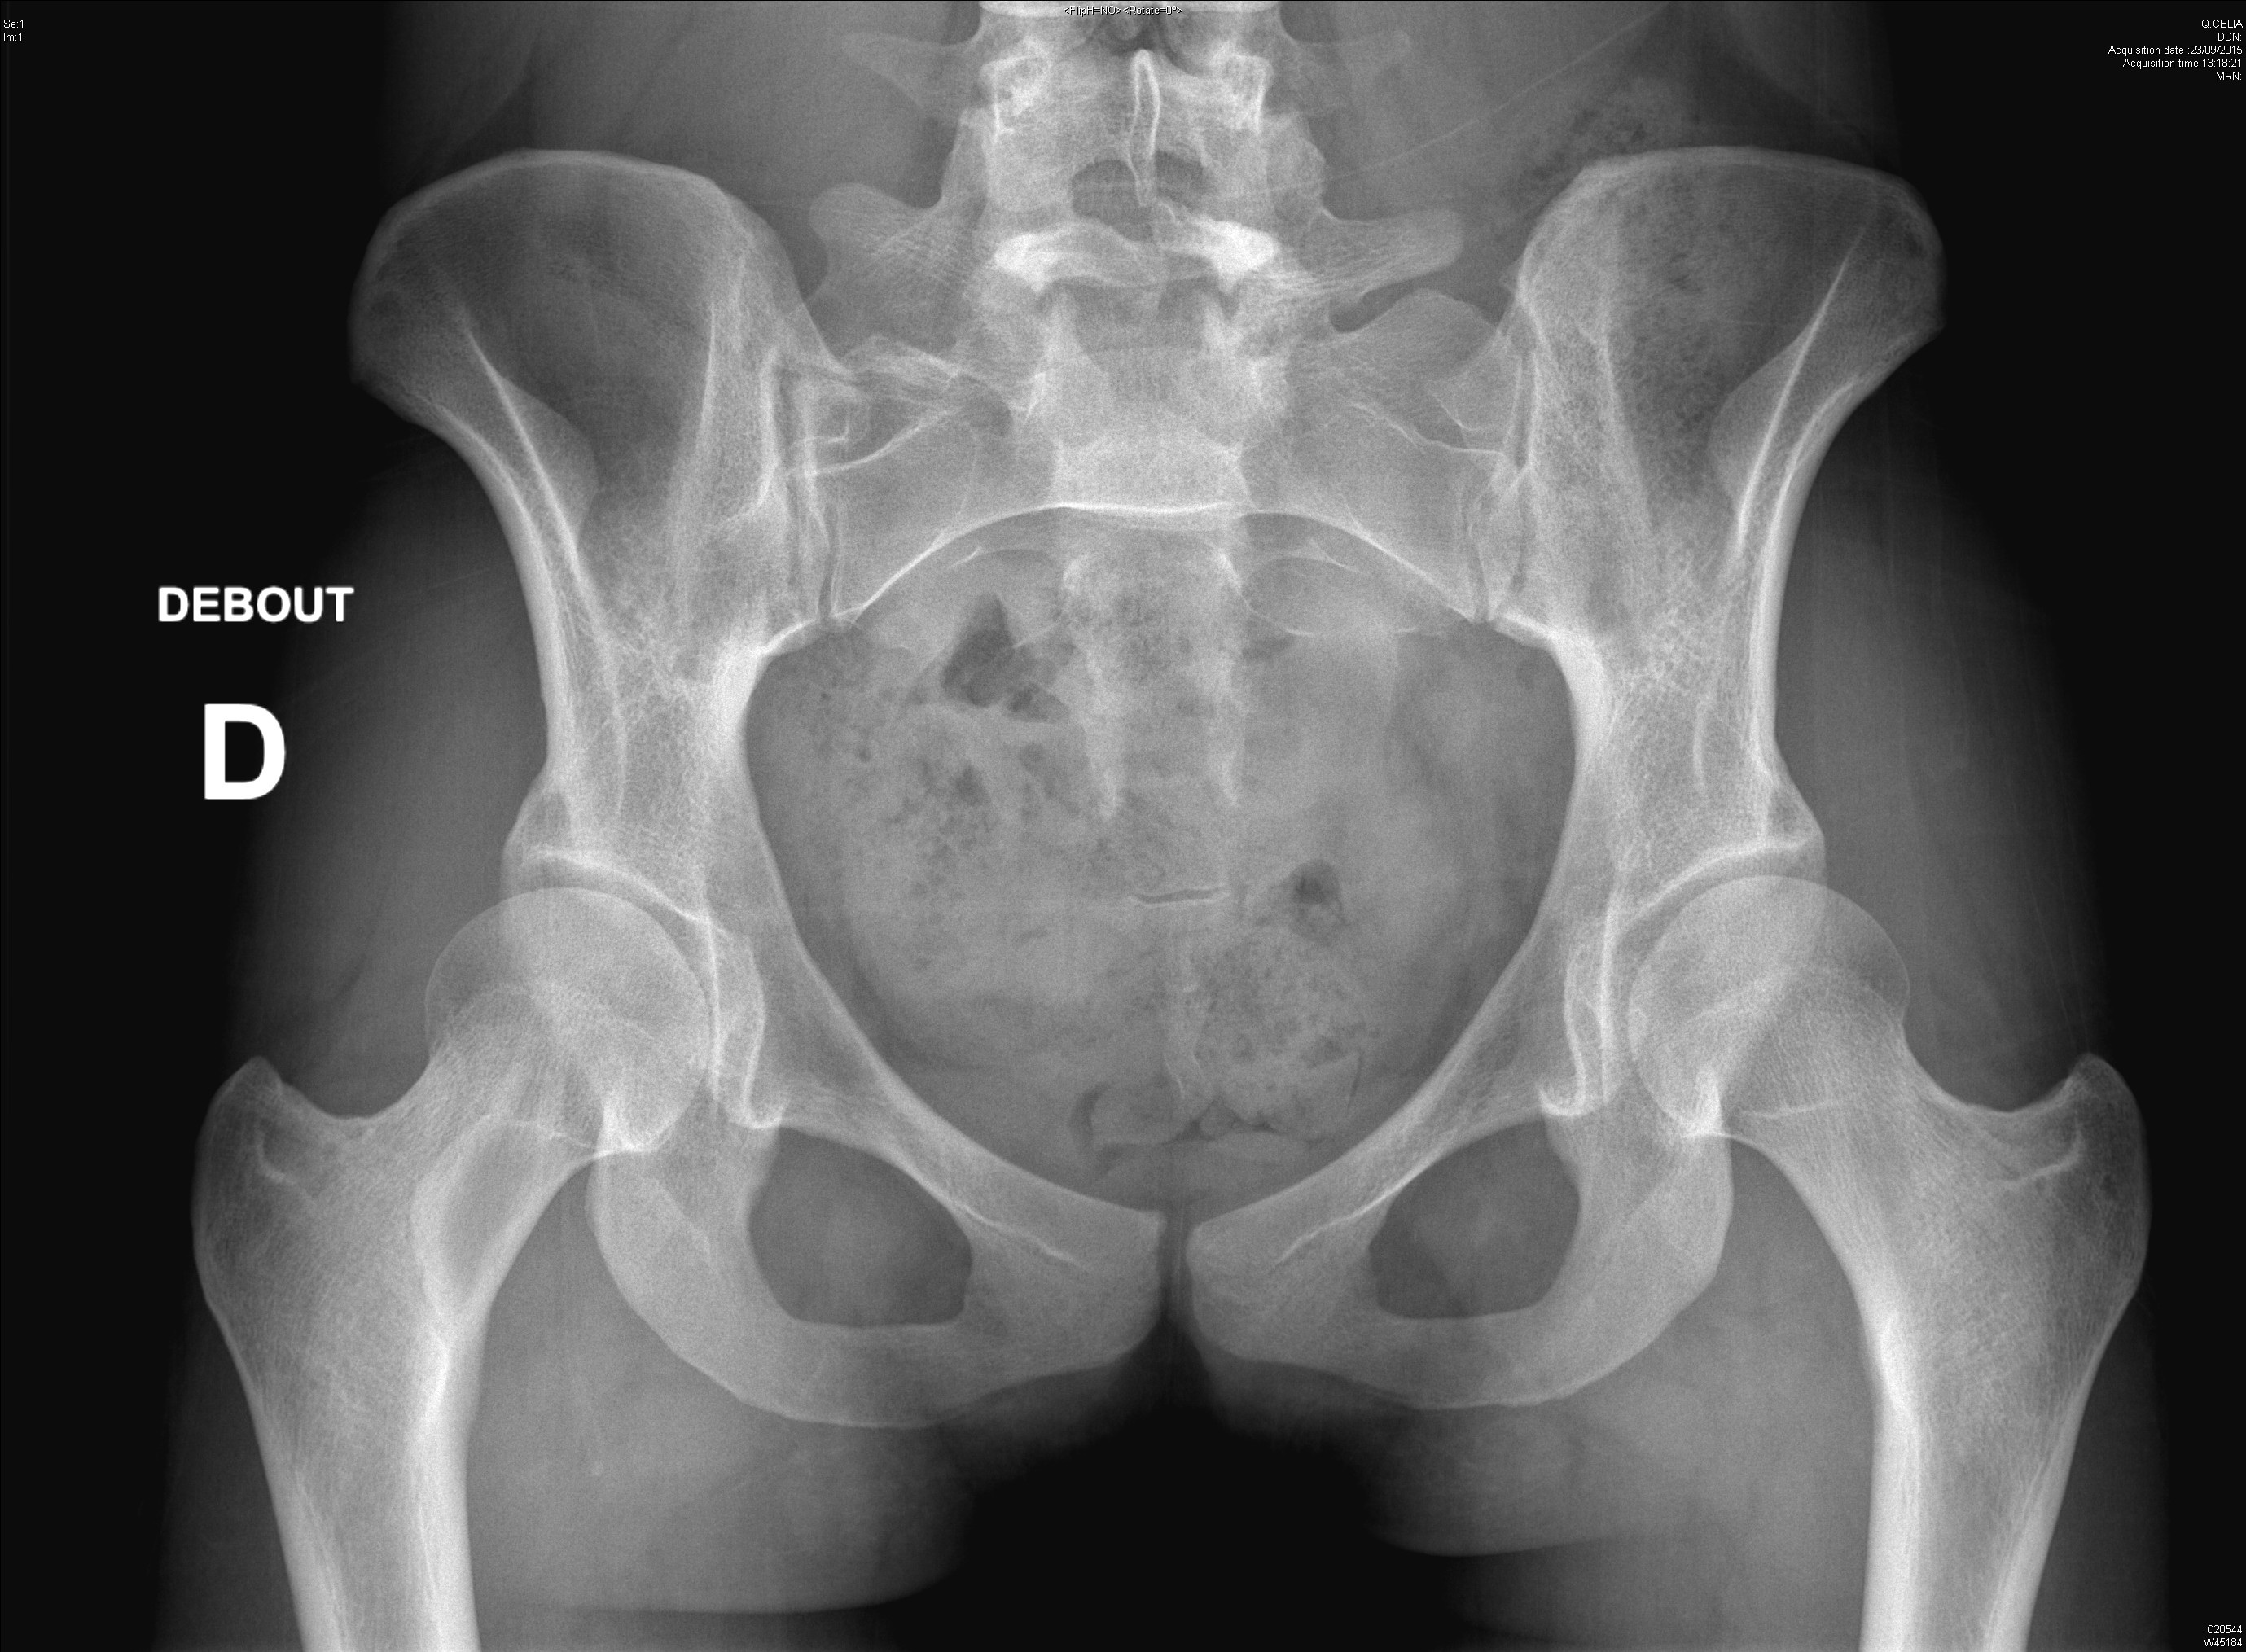

Coxite rapidement destructrice avec ostéonecrose chez une patiente traitée dans le cadre d'un syndrome des anti-synthétases

Radiographie retrouvant une dysplasie acétabulaire bilatérale ainsi qu'une lésion de dysplasie fibreuse du col fémoral droit chez une jeune fille